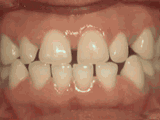

Patient was bothered by the spaces between his teeth. Braces closed the spaces and gave him an ideal bite in twenty-four months. Special glued-in retainers help keep the spaces closed.